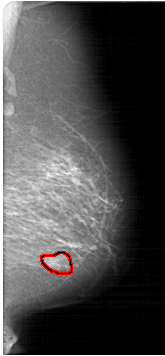

RIGHT_MLO LINES 6391 PIXELS_PER_LINE 2956 BITS_PER_PIXEL 12 RESOLUTION 43.5 OVERLAY

FILE: A_1371_1.RIGHT_MLO.OVERLAY

TOTAL_ABNORMALITIES 1

ABNORMALITY 1

LESION_TYPE MASS SHAPE LOBULATED MARGINS OBSCURED

ASSESSMENT 4

SUBTLETY 3

PATHOLOGY BENIGN

TOTAL_OUTLINES 1

BOUNDARY